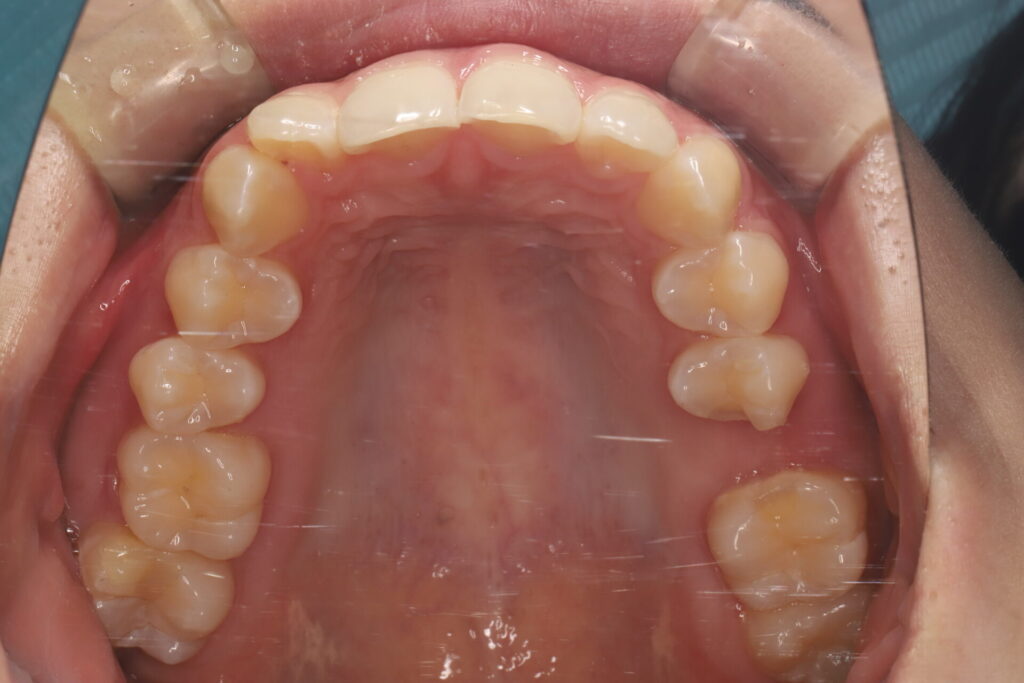

骨格分析に基づき、欠損部にインプラントを入れず、インビザライン(マウスピース矯正)でスペースを閉鎖しながら歯並びと咬合を同時に改善しました。

他院で「インプラントは難しい」と説明を受けた20代女性から、インプラント希望でご相談。精査の結果、矯正でのスペース閉鎖が適応と判断しました。

- 診断:CBCT・口腔内スキャン・咬合解析で移動量と方向を定量化

- 設計:IPR+アタッチメントでミリ単位に歯を再配置

- 結果:スペース閉鎖+配列改善により、見た目・発音・咬合安定・清掃性が向上